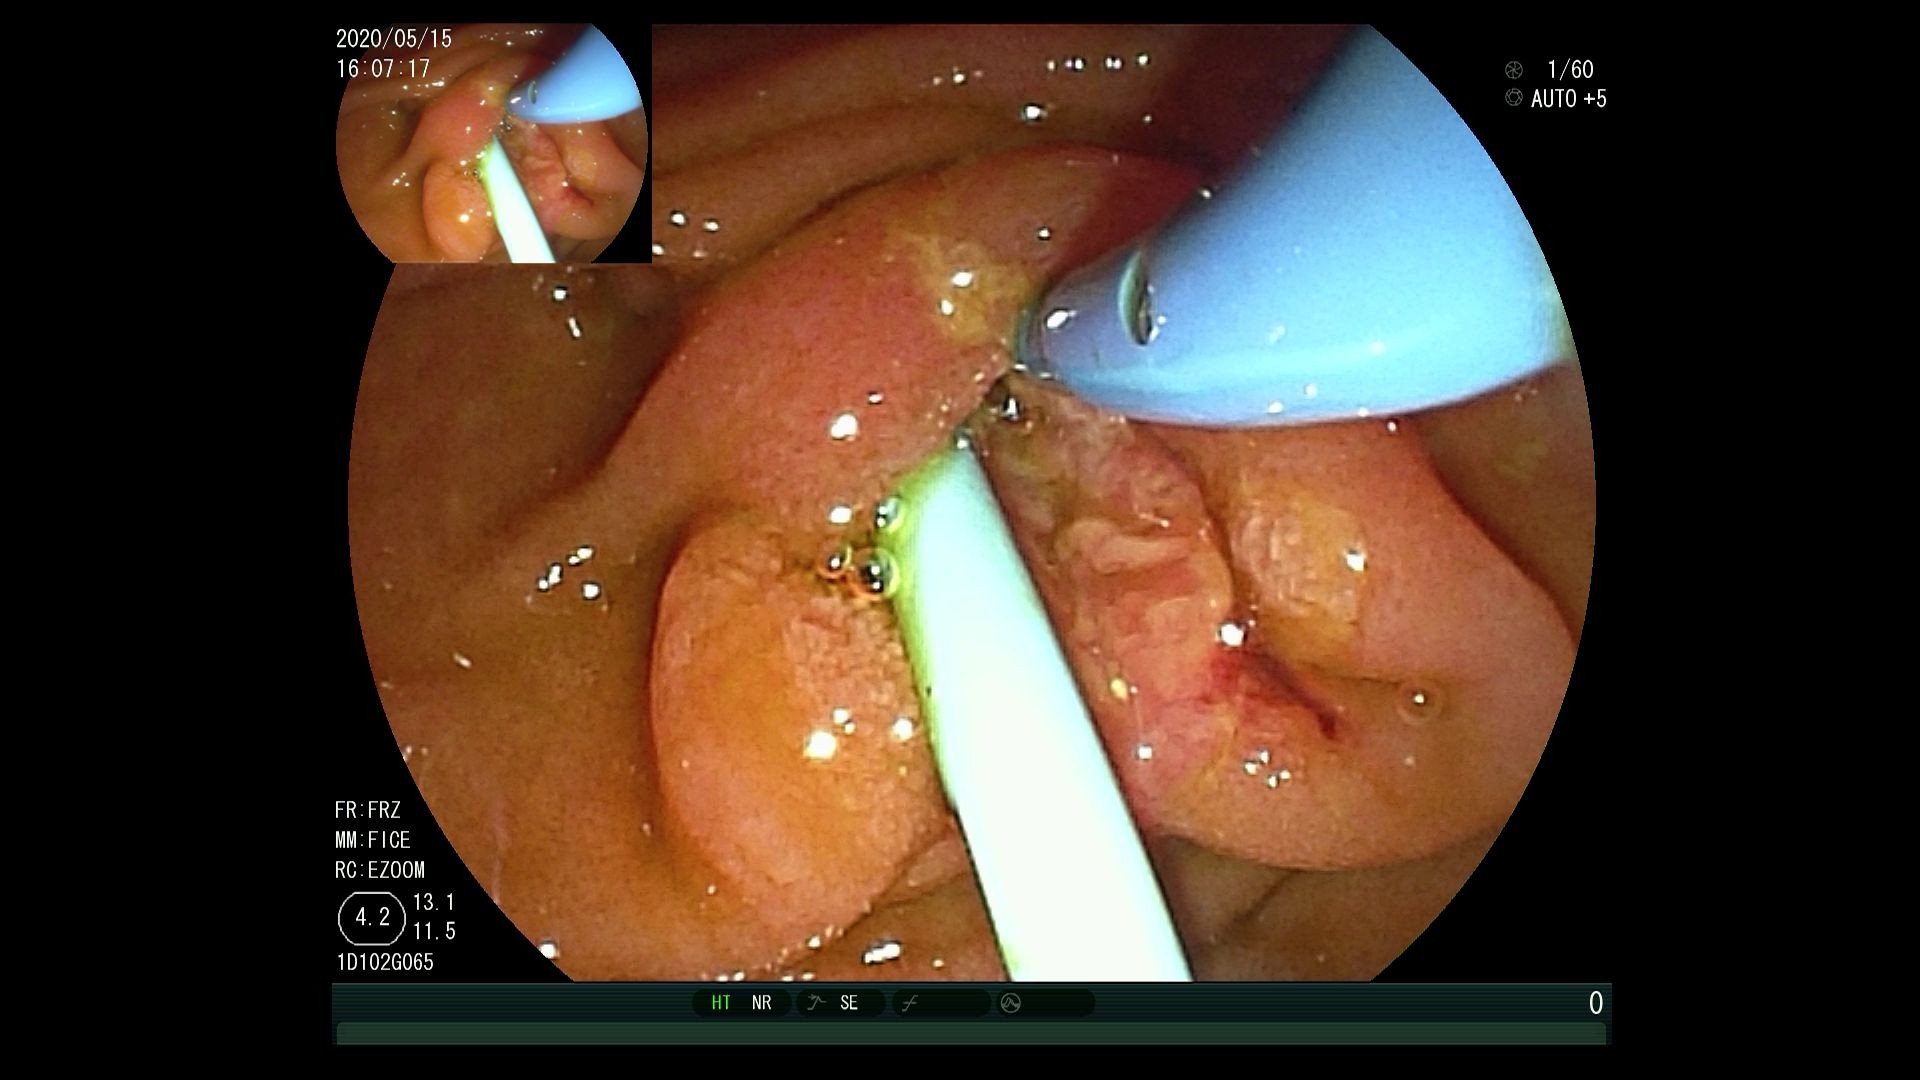

对于高龄患者,或已经有转移的,无法进行手术治疗的患者,经内镜逆行胰胆管造影术(ERCP)放置胆道支架,解除胆道梗阻,减黄治疗是主要的方法,可明显延长生存期,提高生活质量,均优于外科手术。同时也可以手术中放置胰管支架,对胰腺癌后期疼痛缓解有非常明显的作用。

支架可以放置金属支架或塑料支架,可以快速减黄,提高生活质量、延长生存期。

(图1:造影下放置胆总管金属支架。图2:内镜下放置胆总管金属支架。图3:同时放置胆道塑料支架和胰管支架。图4:放置金属支架同时放置放射粒子支架局部放疗)